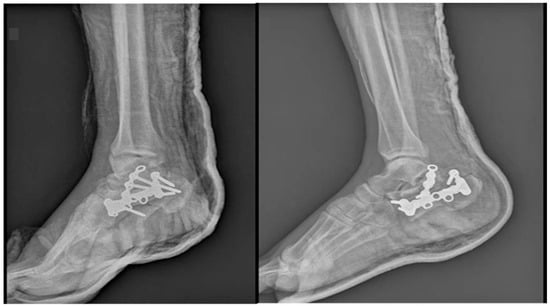

Figure 2. X-rays on the day of presentation in the Emergency Room (A), right calcaneus. (B) left calcaneus.

A 38-year-old male without any other comorbidities presents to the hospital following a fall (approximately 2.5 m in height). The patient complained about the pain at the level of both heels. Locally, we have identified important edema of the right foot and moderate edema of the left, spontaneous and palpatory pain at the level of both heels, and the impossibility of weight bearing. By performing X-rays and CT scans of both distal lower limbs, we have made the primary diagnosis: Bilateral calcaneal fracture, highly comminuted on the right side (Müller/AO/OTA: 82-C3) with moderate displacement and no comminution or displacement on the left side (Müller/AO/OTA: 82-A2). Figure 2. Because of the important edema, the surgery has been postponed for 7 days, during which the patient received thromboprophylaxis, pain killers, and local therapy (elevation of the limbs, local cryotherapy) while having a bilateral cast immobilization.